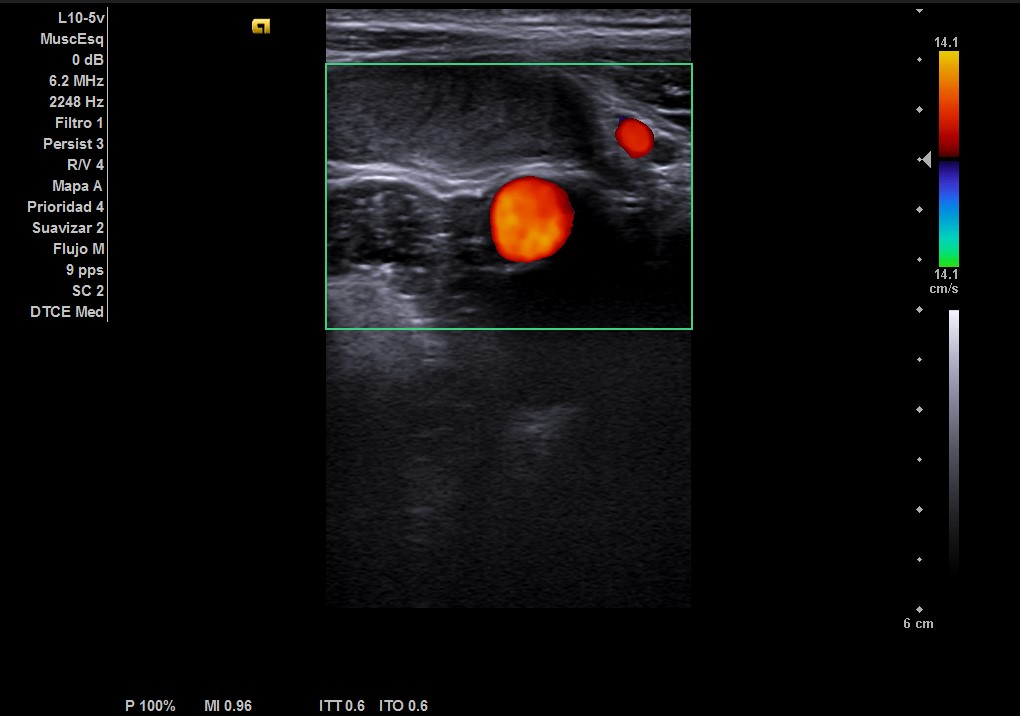

Durante la realización de la prueba, el paciente comenta que en ocasiones no encuentra el testículo derecho. Por lo que decidimos cambiar a la sonda lineal y explorar planos más superficiales donde observamos el testículo derecho, por encima del ligamento inguinal, en fosa ilíaca derecha con ecoestructura normal, homogénea y vascularización normal.

Teste derecho en ascensor.